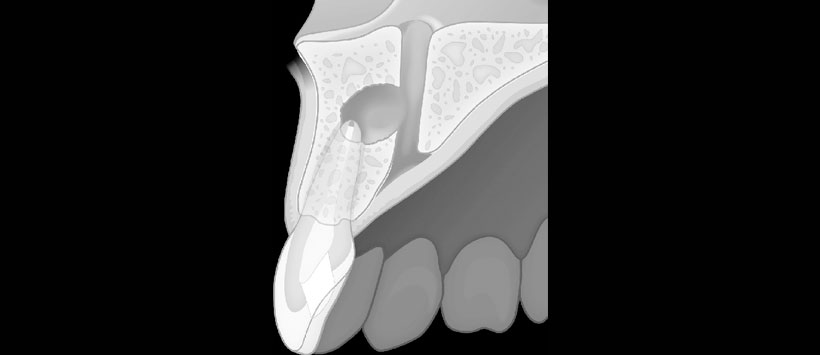

Los resultados mostraron que en el grupo de trauma (n = 96), el 31,3% tenía al menos un incisivo maxilar perdido y el 95,8% tenía incisivos con tratamiento de endodoncia. La dimensión anteroposterior del foramen incisivo (p = 0.02) y del CNP a mitad de camino (p = 0.04) fue significativamente mayor en el grupo de trauma. Significativamente se evidenció más casos con un signo abultado en el grupo de trauma (n = 19) que en el grupo control (n =3, p = 0,001). Se identificó una osteólisis apical en el 5,1% de incisivos, y 12/38 mostraron una fusión con el CNP.

El estudio concluyó que dimensiones más amplias del CNP y un signo abultado puede sugerir una lesión dentoalveolar anterior en el maxilar anterior. La osteólisis periapical del incisivo central de más de 5 mm de diámetro tiende a fusionarse con el CNP.

- Figura 4: Ilustración esquemática de una lesión osteolítica apical de la raíz de un incisivo maxilar que muestra la fusión con el canal nasopalatino